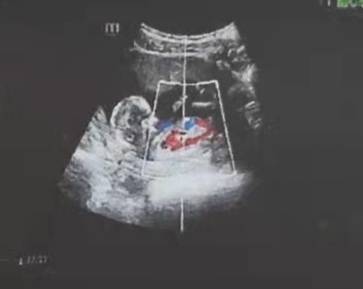

能看出男孩女孩吗

journal_insert_pic_1674605076journal_insert_pic_1674605081

这是看不出来的呀,从这些体检报告单上是不能看出宝宝是男生女生的,只要知道宝宝发育的一切健康就好